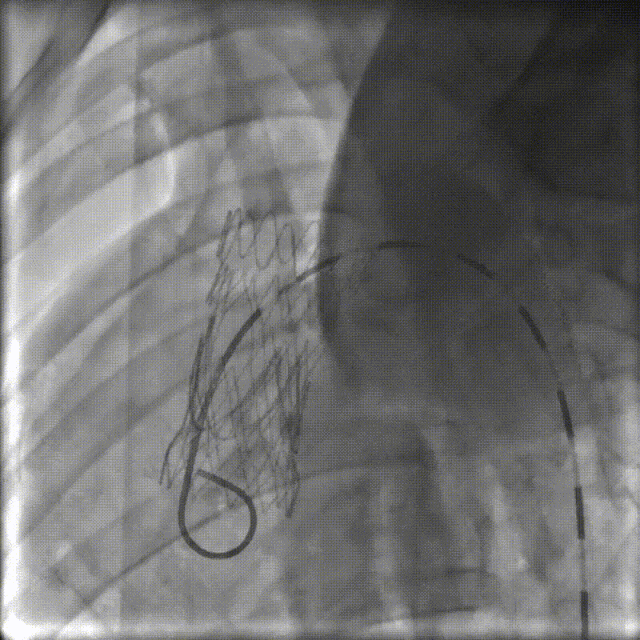

目前专家共识的一个重要遗憾是未涉及根部夹层的带瓣腔内修复。主动脉根部夹层常合并瓣膜撕裂、瘤样扩张等问题,传统治疗面临巨大挑战。针对这一难题,研究团队提出瓣窗型腔内移植物对根部夹层腔内治疗,已获得上海市科委启明星计划(40万)、上海市卫健委新兴前沿技术(100万)、上海市科委重点项目(100万)等多项基金支持,累计经费超200万元。

2020年,团队首次报道成功的主动脉根部腔内重建动物实验,发表于JACC(IF=20.6)。实验结果显示:手术时间控制在1小时内,术后第2天动物可自行进食,长期存活率达97.2%。这一突破为未来临床转化奠定了坚实基础

针对升主动脉根部病变,目前有两条技术发展路径:

路径一:Off-label PMEG(经导管瓣膜增强移植物)

路径二:专用腔内移植物研发

国际上,欧美先锋术者已率先施行成功的“ENDO BENTALL”手术,采用双向入路(Rendez-vous access),虽无需改装移植物,但存在循环崩溃风险,需ECMO支持,且有心尖入路相关风险。新的专用器具也在国外研发中。